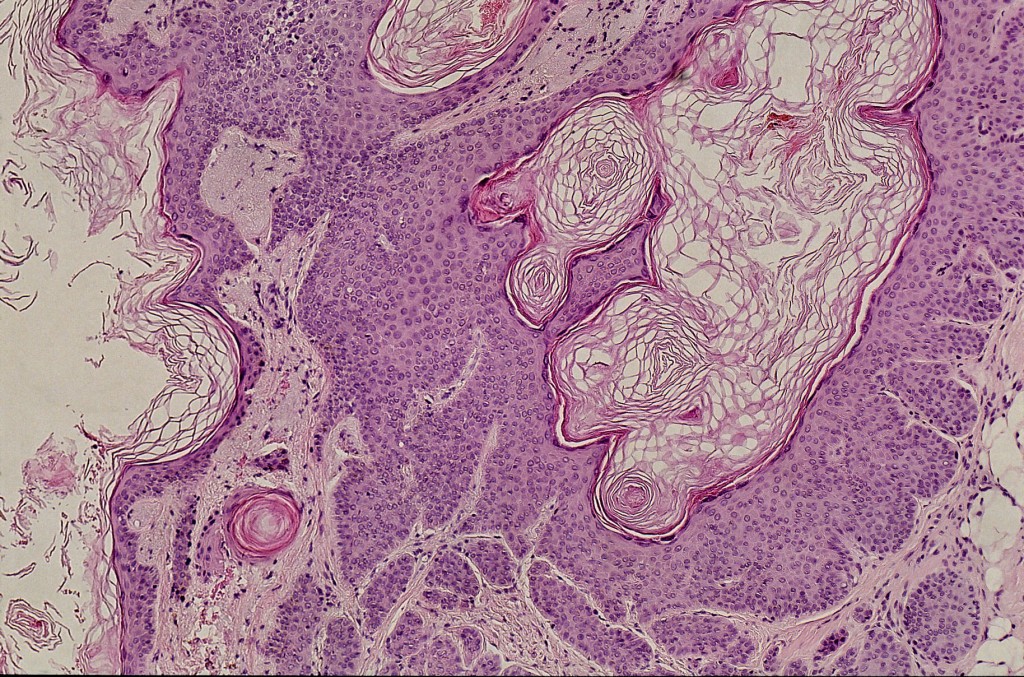

PA:

Meestal een verticaal georiƫnteerde proliferatie van epitheel met een grote

centrale holte die met een nauwe opening in verbinding staat met de buitenwereld.

De holte is bekleed met keratinocyten en gevuld met compacte basket-weave lagen

hoorn. Vaak rondom in de dermis lobuli van eosinofiel aankleurende cellen die

met de centrale holte in verbinding staan. De DD histologisch is een dilated

pore van Winer en een trichofolliculoma.

![Pilar sheet acanthoma (click on photo to enlarge) [source: www.huidziekten.nl] Pilar sheet acanthoma](../../../images/pilar-sheath-acanthoma-3-PAz.jpg) |

![Pilar sheet acanthoma (click on photo to enlarge) [source: www.huidziekten.nl] Pilar sheet acanthoma](../../../images/pilar-sheath-acanthoma-4-PAz.jpg) |

| pilar

sheet acanthoma (PA) |

pilar